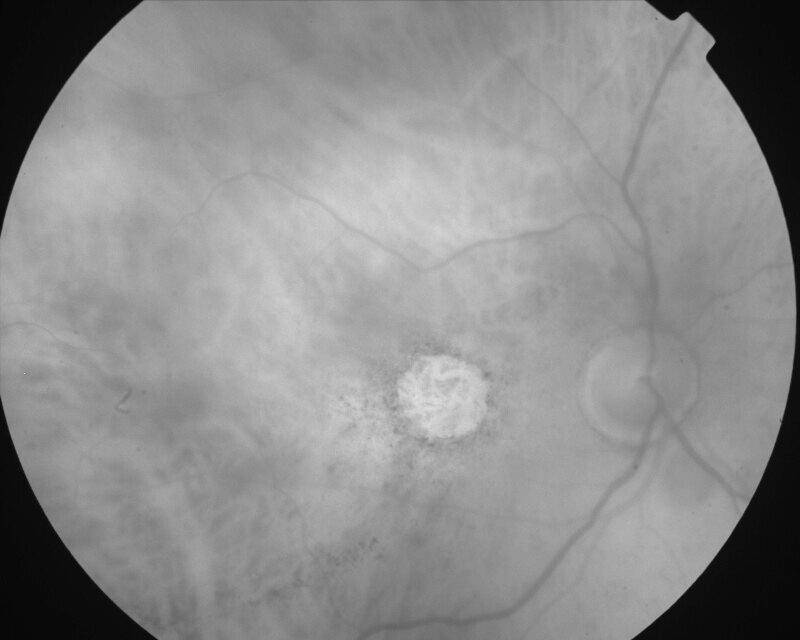

ATROPHIE AREOLAIRE CENTRALE

IMG0007.jpg